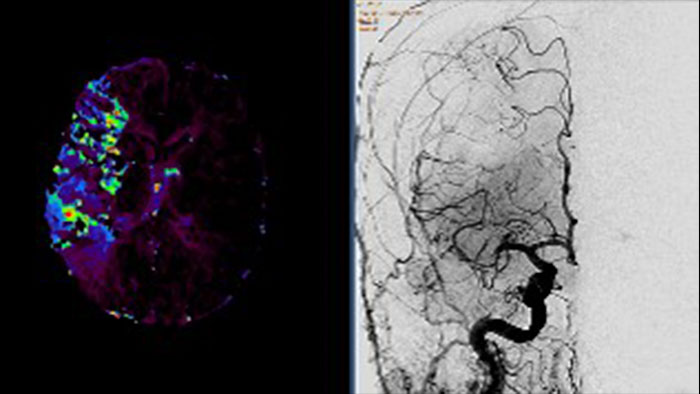

Contrast arterial structures with surrounding bone and soft tissue to assist in identification of vascular abnormalities

The XA Vascular Processing – DSA (in MMV) expands your workflow by allowing you to read and post-process iXR images virtually anywhere. Obtain images of arteries in various parts of the body using tools to perform standard and run subtractions, pixel shifting, and landmarking. This application also provides post-processing tools to edit and optimize the DSA XA data created in the interventional room.

Comprehensive reviewing tool for multiple modalities, all in a single viewer

The Multi Modality Viewer (MMV) now supports viewing and post processing of angiography images and series. Review and perform analysis of angiographic imaging alongside other modalities for a comprehensive review of the patient case. Perform vascular processing of images (Digital Subtraction Angiography) – subtraction, pixel shifting and land marking. Include key images into the generic MMV report. Prior to the intervention, relevant diagnostic (MR and or CT) data can be bookmarked and automatically retrieved upon patient selection in the Allura, or the Azurion suites.